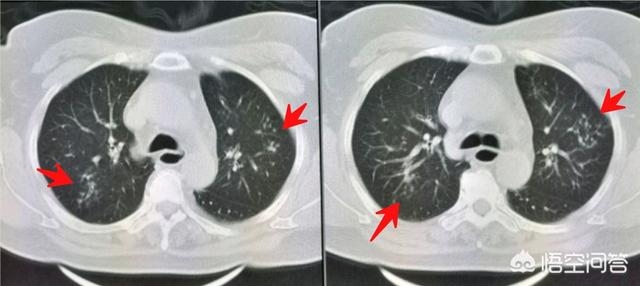

挂了呼吸科专家号,医生说做个肺部CT吧,这个年纪应当查一下:

胸部CT发现双肺多发小斑点状影,提示沿支气管扩散的肺内炎症。